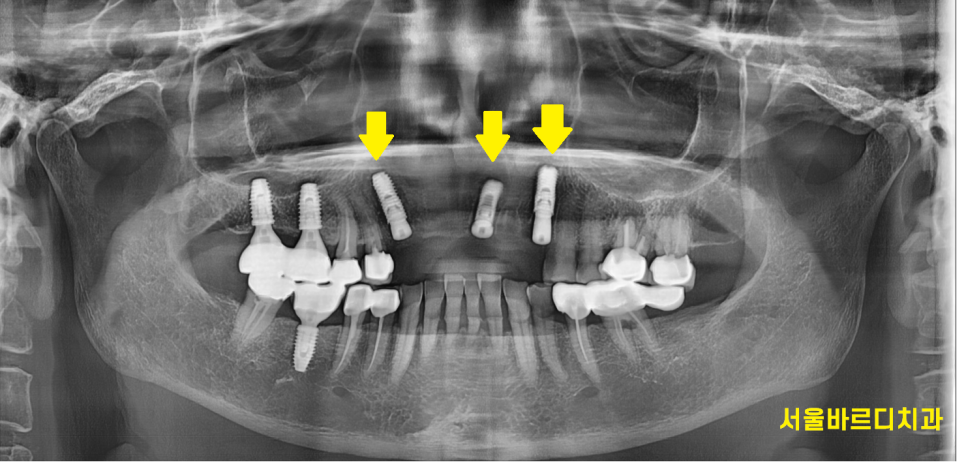

240315

앞니 브릿지 발치를 하면서 임플란트 바로 식립해드렸습니다.

이전 글에서 말씀드렸다 싶이

앞니는 뼈가 얇습니다.

그래서 뼈가 수축하기 전

발치와 동시에 수술을 하는데요.

치료기간도 단축된다는 장점이 있죠~

240731

4월에 수술을 하고 3개월정도 지나

머리를 만들어 드렸는데요.